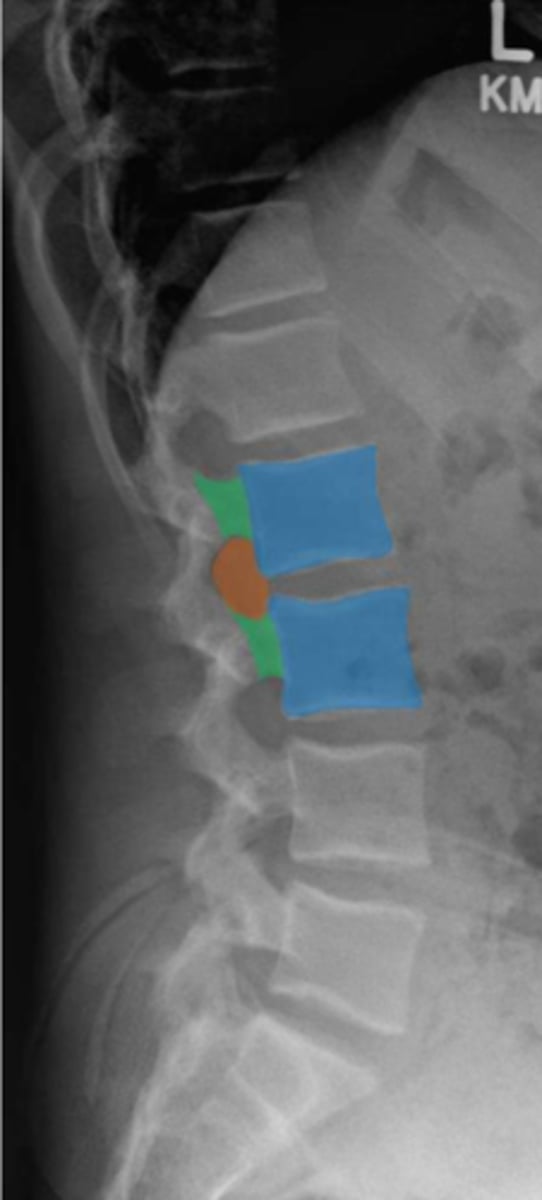

lumbar

What vertebrae is being examined?

lumbar vertebral body

Identify the blue structure

pedicles

Identify the green structure

transverse processes

Identify the purple structure

spinous processes

Identify the yellow structure

joint space between superior and inferior articulating facets

Identify the red line

intervertebral foramen

Identify the orange structure

pedicles

Identify the green structure

spondylolysis

pars interarticularis

oblique view

What condition is being examined for in this radiograph?

What structure is it looking for?

What view is this radiograph in?